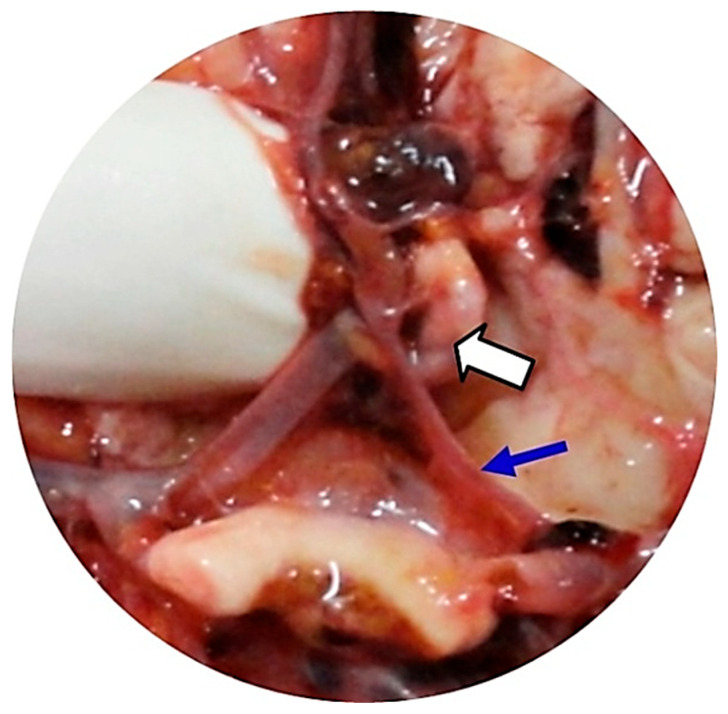

Methods: We investigated the anatomical variants of the CW associated with the occurrence and rupture of AcoA aneurysms by performing comparative analyses, in the same patients, of postmortem autopsy data with antemortem computed tomography-angiography (CTA) results obtained in the first 48 h after the onset of subarachnoid hemorrhage. Our retrospective observational study identified the anatomical variants of the CW at autopsy in 16 deceased adult Romanian patients with AcoA aneurysms over a 12-year period (2010-2022).

Results: The autopsy findings revealed that the AcoA ruptured aneurysms had a mean external diameter of 9.50 mm, and 71.4% of them presented three or four anatomical variants inside the same CW. The initial antemortem CTA examination correctly located the AcoA aneurysms in all cases (100%), and an anatomical variant of the CW was only noted in 18.75% of patients. The final postmortem re-analyzed the same CTA images identified in all cases (100%), focusing on both the AcoA aneurysm and all anatomical variants of the CW found during the autopsies.